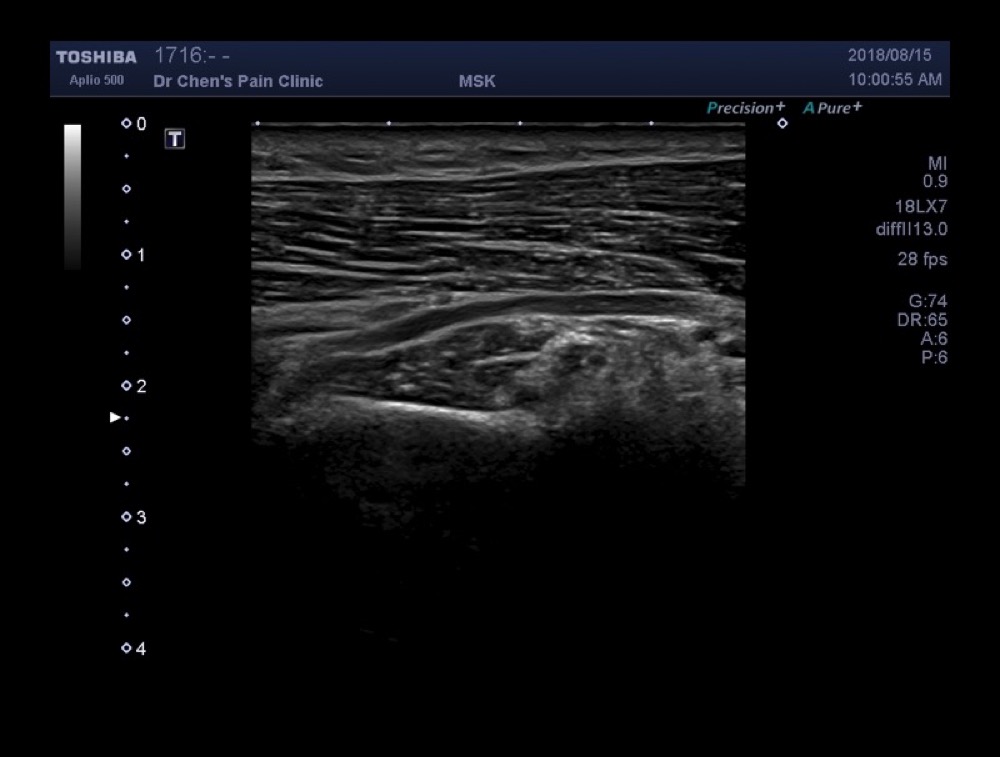

Radial nerve Cross spiral groove

(錄影)Radial nerve穿過spiral groove的時候,會由蜂巢狀的神經變為只剩下一大圈的神經,這是正常的,不代表病變。